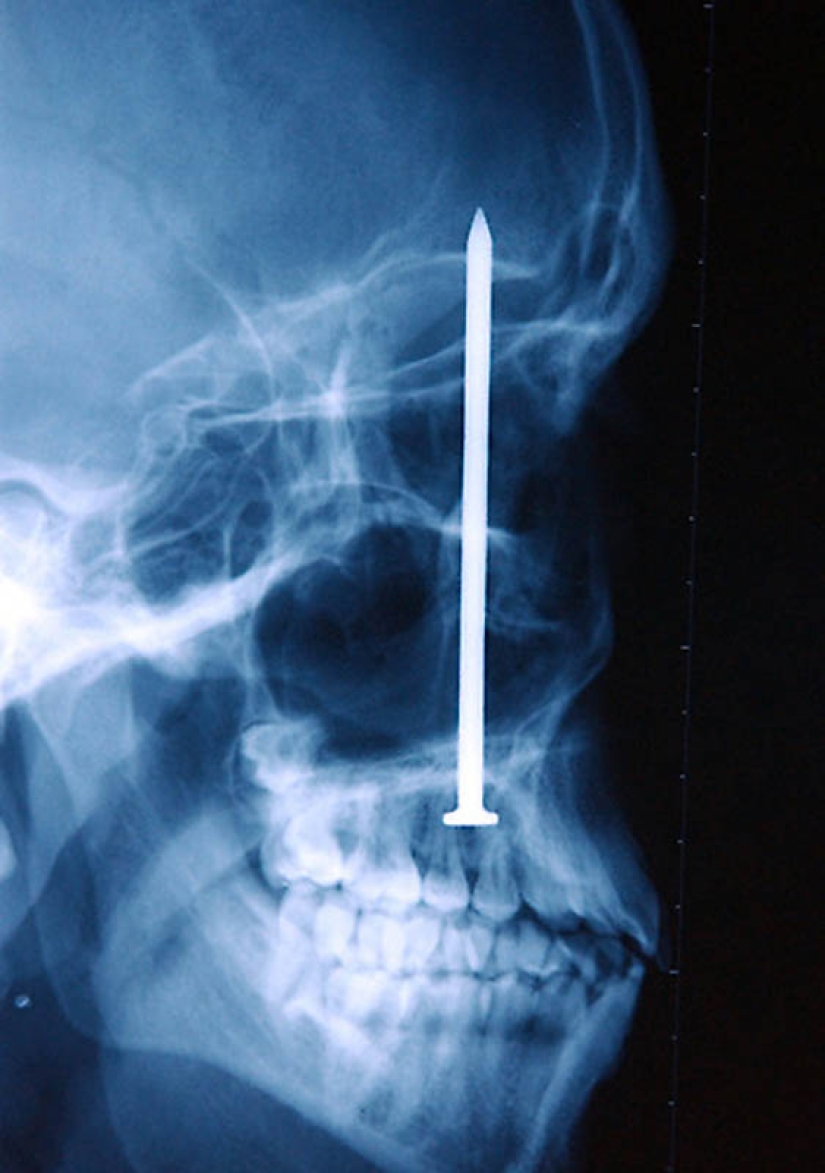

13. Clavo en el cráneo humano: el paciente se disparó accidentalmente con un martillo neumático. Ni siquiera se dio cuenta de que se había disparado a sí mismo – un clavo de 10 cm de largo fue encontrado solo después de 6 días.